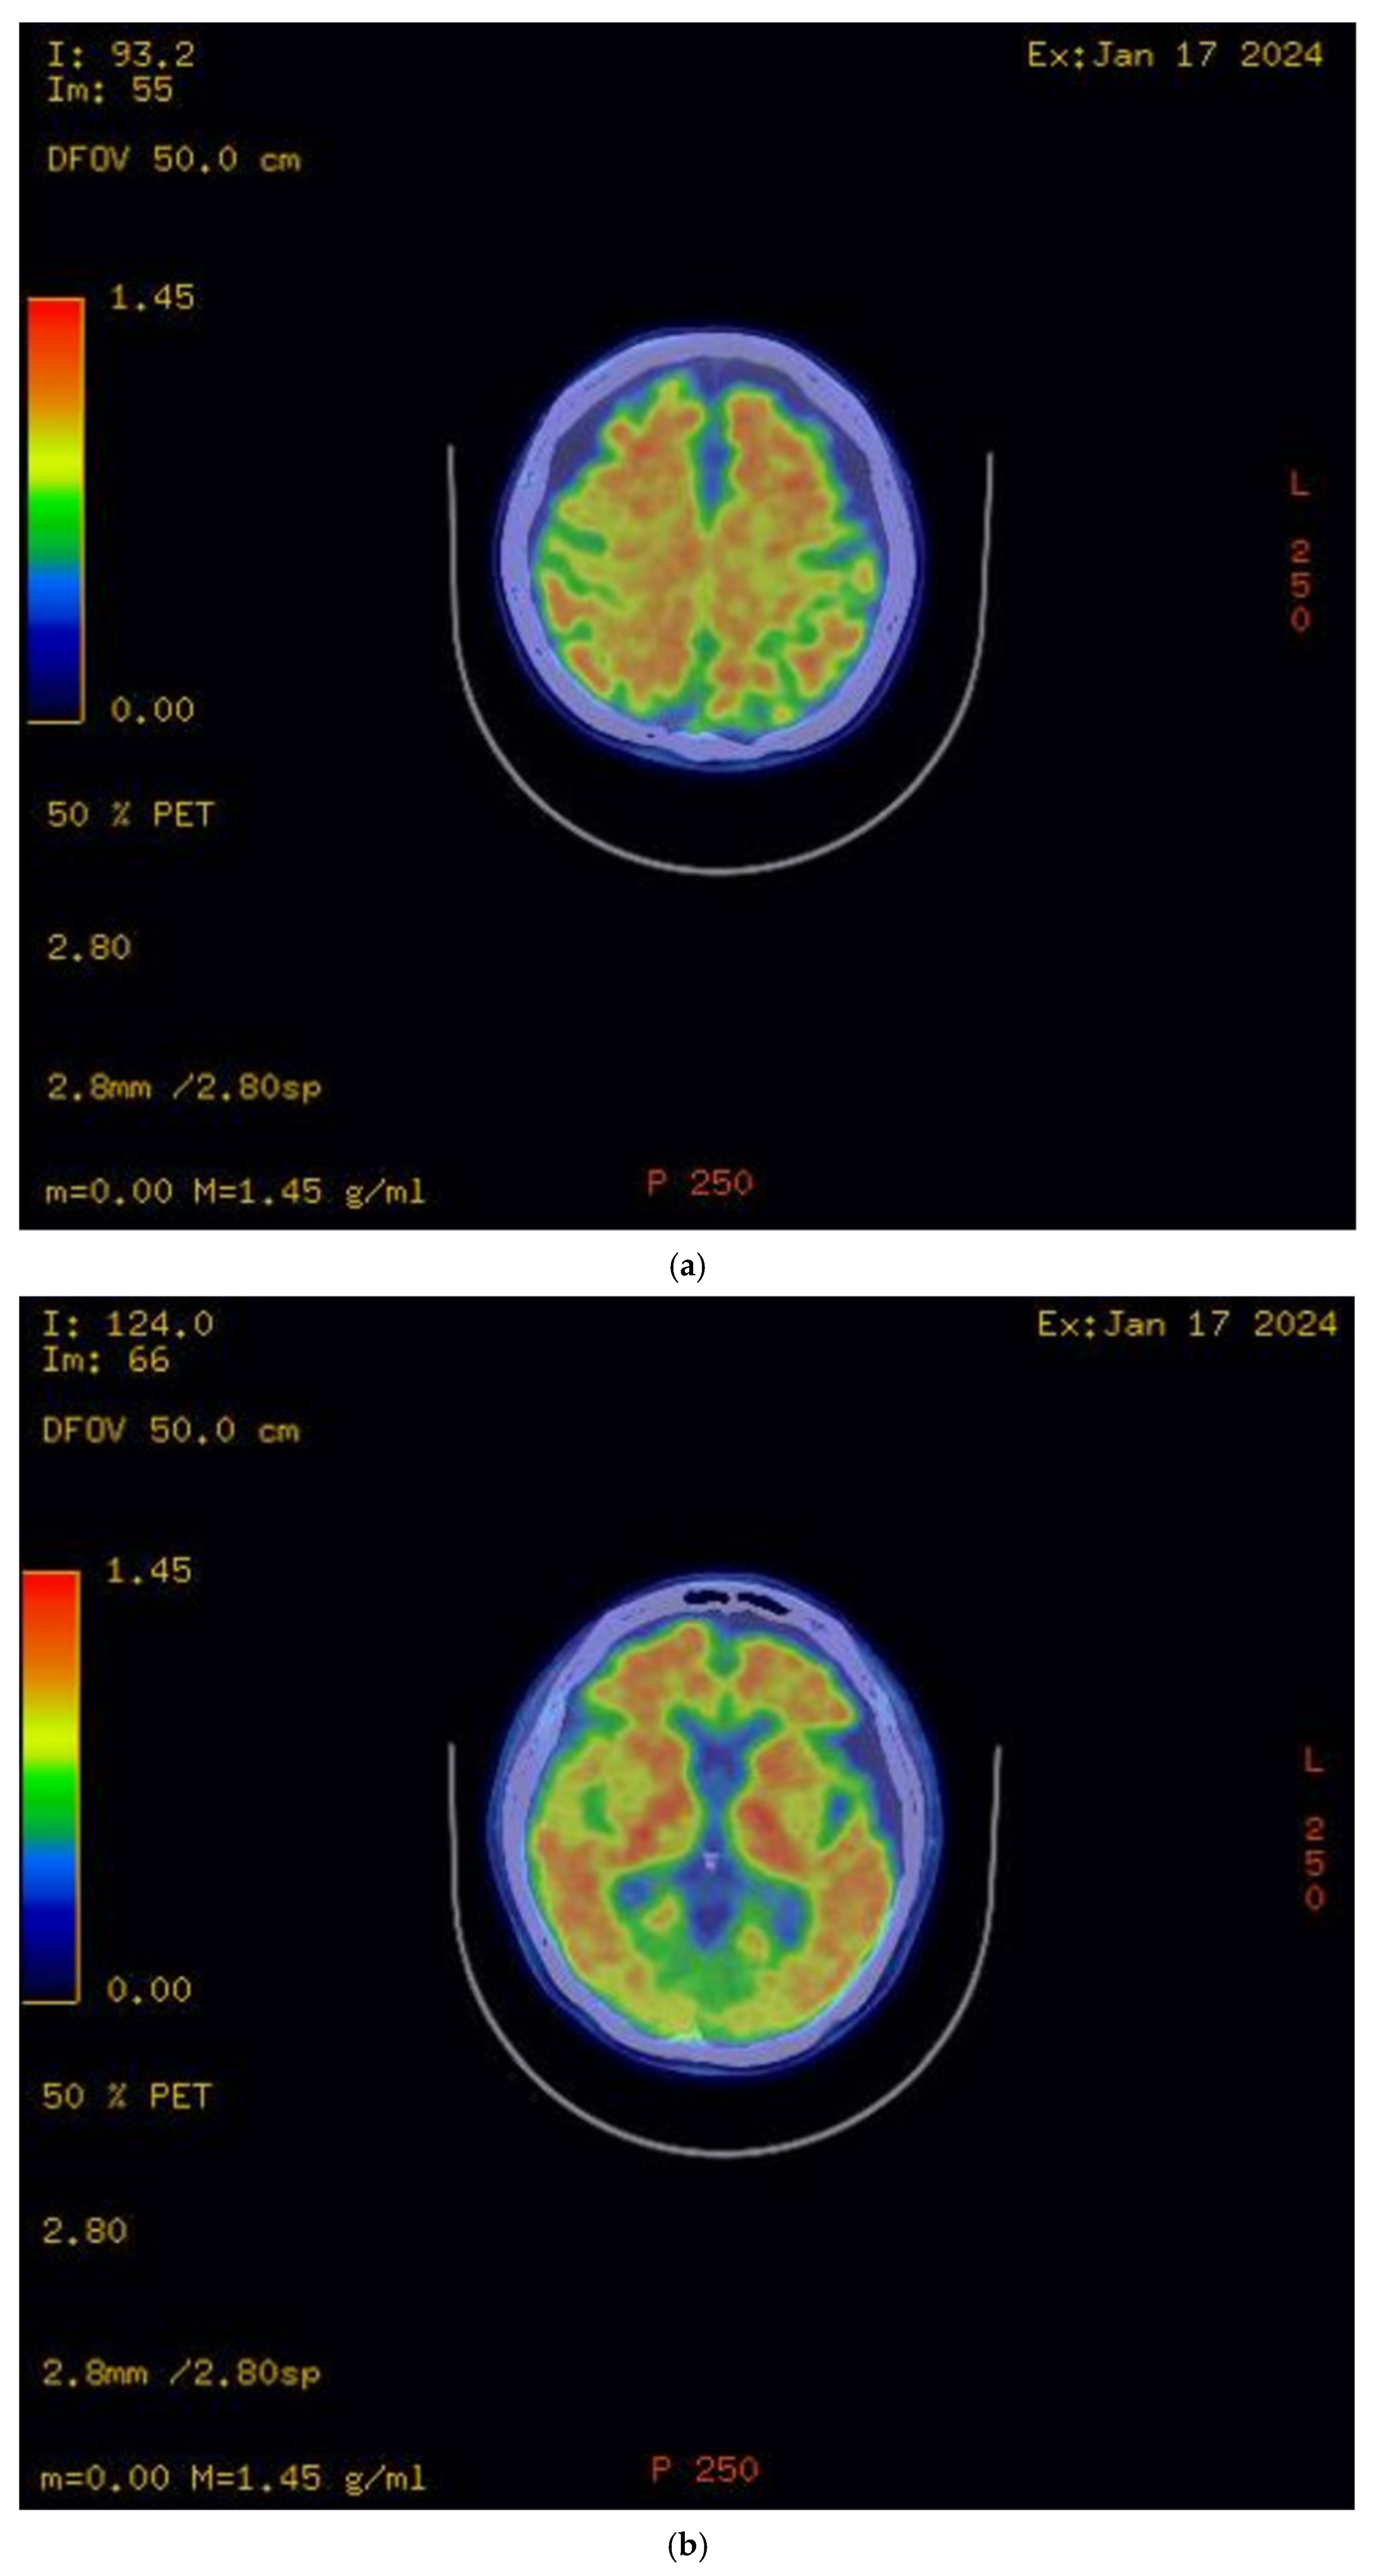

The initial brain MRI conducted in March 2023 demonstrated global cerebral involution with equivocal frontoparietal predilection and relative medical temporal lobe sparing. Global cortical atrophy (GCA) grade 1–2 was reported, showing mild to moderate brain atrophy with a reduced gyri volume, increased sulci and moderate ventricular dilatation [5]. There was evidence of progressive neurodegenerative changes in the brain MRI findings one year later; the second brain MRI in April 2024 showed predominant bilateral frontal and parietal volume loss, sparing the occipital and temporal lobes. A medial temporal lobe atrophy score (MTA) of grade 1 was reported (Figure 2). Amyloid positron emission tomography (PET) (Figure 3) confirmed the presence of amyloids, a hallmark of Alzheimer’s disease. While a lumbar puncture to measure cerebrospinal fluid (CSF) biomarkers (Aβ1-42 and tau) was offered, the family declined due to the invasive nature of the procedure.

Figure 3.

Amyloid PET scan. (a) Radiotracer uptake detected in bilateral frontal and parietal lobes; (b) radiotracer uptake detected in bilateral temporal lobes.